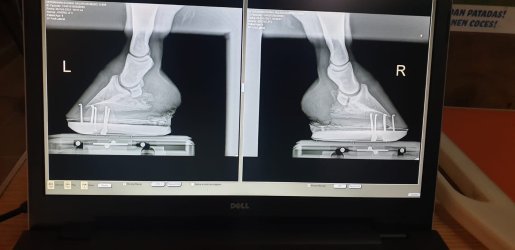

Y aquí el primer herraje con Canes, más recientes no tengo: